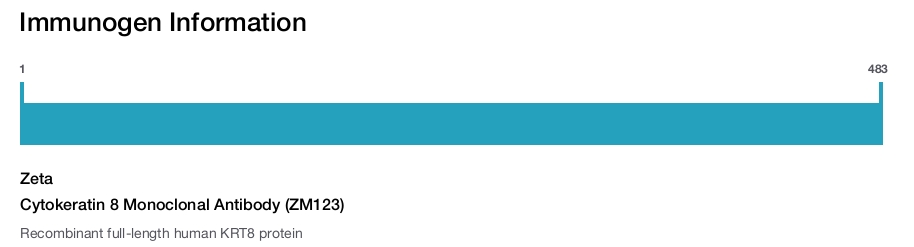

Zeta

Cytokeratin 8 Monoclonal Antibody (ZM123)

Cytokeratin 8 is a member of the type II keratin family clustered on the long arm of chromosome 12. Type I and type II keratins heteropolymerize to form intermediate-sized filaments in the cytoplasm of epithelial cells. Cutokeratin 8 typically dimerizes with keratin 18 to form an intermediate filament in simple single-layered epithelial cells. This protein plays a role in maintaining cellular structural integrity and also functions in signal transduction and cellular differentiation. Mutations in this gene cause cryptogenic cirrhosis.

蛋白别名: CK-8; Cytokeratin-8; K8; keratin 8, type II; Keratin, type II cytoskeletal 8; Keratin-8; Type-II keratin Kb8

基因别名: CARD2; CK-8; CK8; CYK8; K2C8; K8; KO; KRT8

UniProt ID: (Human) P05787

Entrez Gene ID: (Human) 3856